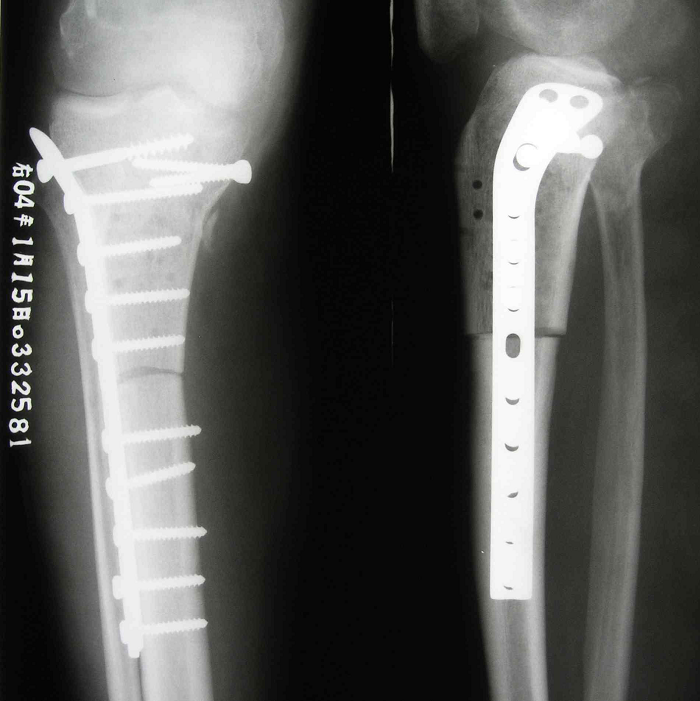

3.病例3:男 48岁, 右胫骨近端骨巨细胞瘤(Campanacci Ⅲ级),行瘤段广泛切除异体半关节移植术

图 14 术后X线片